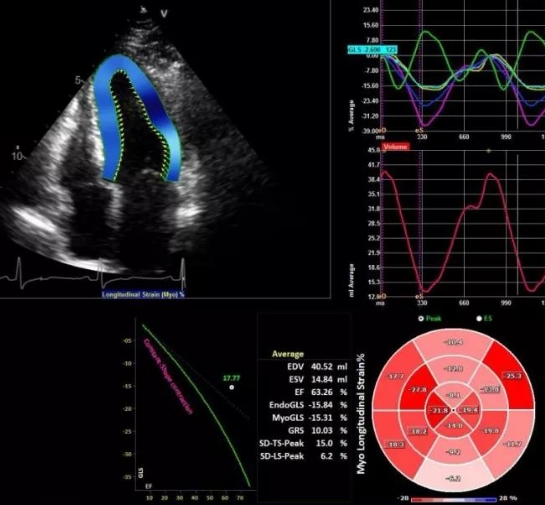

無創(chuàng)心臟成像的新選擇:實(shí)時(shí)三維超聲心動(dòng)圖設(shè)備的功能與優(yōu)勢(shì)

實(shí)時(shí)三維超聲心動(dòng)圖設(shè)備是一種先進(jìn)的醫(yī)療成像設(shè)備,主要用于心臟結(jié)構(gòu)和功能的評(píng)估。以下是關(guān)于該設(shè)備的產(chǎn)品簡(jiǎn)介、功能使用方法以及維修保養(yǎng)的…

三維超聲心動(dòng)圖設(shè)備

三維超聲心動(dòng)圖設(shè)備特點(diǎn)

三維超聲心動(dòng)圖設(shè)備采購(gòu)